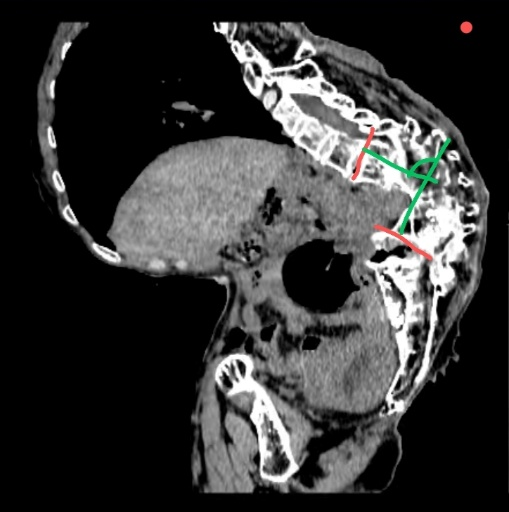

患者因“绝经后阴道流血10天,诊刮病理提示子宫内膜样腺癌”入院。该患者其幼年曾患结核,导致严重脊柱后凸侧弯(俗称“罗锅”),无法平卧,手术时仅能耐受接近坐位的特殊体位,这导致手术操作空间严重受限、暴露困难,术中极易损伤脊柱脊髓,术后拔管困难与低氧血症风险高,加之患者先天性聋哑,医患沟通存在障碍,手术难度与风险极高。